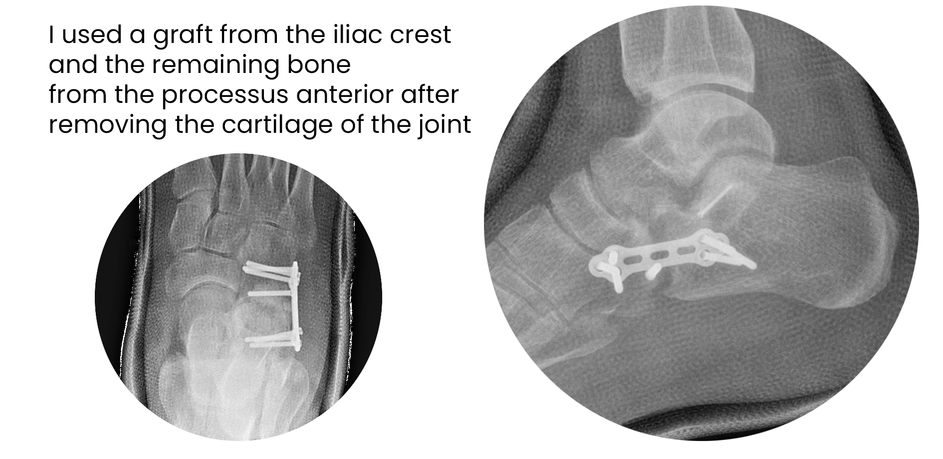

case 17LC, 29 years old, female, fall from horse

with the foot caught in the stirrup

"atypical fracture", surgery 19 hours after trauma